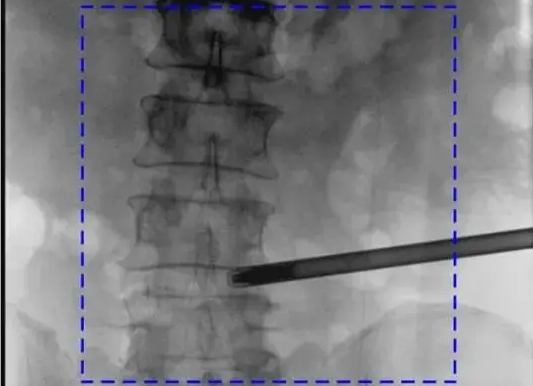

三維C形臂與二維C形臂臨床圖像實時對比

移動式C形臂X射線機有著二維和三維之分,它們都具備透視與攝影功能,能夠為醫(yī)生提供術(shù)中影像引導。三維C形臂采集的圖像究竟比二維C形臂好在哪?下面我們結(jié)合臨床病例的影像來解答!...